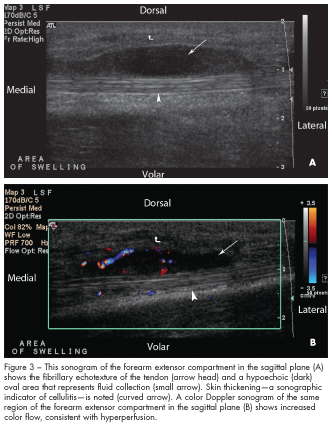

In this case, the sonographic images were obtained using a Philips HDI 5000 with a 12-5 Hz linear transducer starting from the dorsal wrist toward the mid forearm. The images (Figures 1A, 2A, and 3A) show the fibrillary echotexture of the tendons (arrow heads), which appear bright.6 These tendons are thickened and surrounded by hypoechoic (dark) oval areas that represent fluid collections (small arrows), which may be edema and/or pus, within the tendon sheaths. Thickening of the tendons and surrounding edema and pus are common findings of tenosynovitis.7,8 Doppler imaging (Figures 1B, 2B, and 3B) shows increased color flow, consistent with hyperper-fusion, which has been shown to be associated with inflammatory changes.9 In addition, skin thickening is present (curved arrows); this is a sonographic indicator of cellulitis.